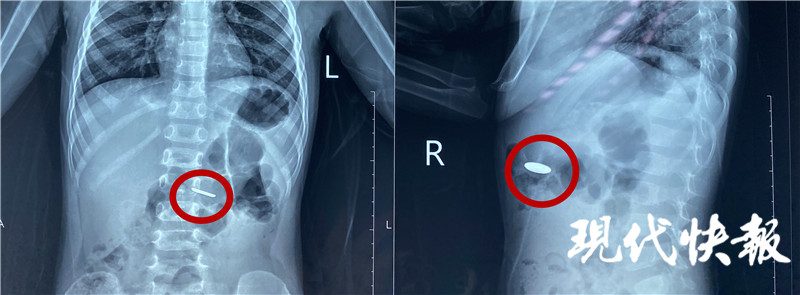

4月20日,江蘇淮安,小豪的家人在收納玩具的時(shí)候,發(fā)現(xiàn)常用的遙控器里的一顆紐扣電池不見了,家人的第一反應(yīng)是電池被小豪吃了,趕緊帶著他前往醫(yī)院。經(jīng)過緊張的手術(shù),醫(yī)生從2歲男童小豪(化名)的小腸內(nèi)取出一枚紐扣電池,電池周圍的腸壁被腐蝕發(fā)黑。

“當(dāng)時(shí)拍了片子發(fā)現(xiàn)電池在胃部,消化內(nèi)科的醫(yī)生及時(shí)給他做了胃鏡檢查,這個(gè)電池比較小,已經(jīng)快速排空進(jìn)入了小腸,胃鏡沒有發(fā)現(xiàn)電池。后來又拍片檢查,確認(rèn)電池已經(jīng)進(jìn)入小腸,就轉(zhuǎn)入外科進(jìn)行手術(shù)治療。”淮安市婦幼保健院小兒外科主治醫(yī)師顧春暉說。

完善手術(shù)準(zhǔn)備,醫(yī)生通過腹腔鏡將電池取出。“這個(gè)手術(shù)本身比較困難,因?yàn)檫@個(gè)電池非常薄,直徑只有1厘米左右,小腸非常長,我們用了很長時(shí)間才找到這個(gè)電池,電池附近的腸道黏膜已經(jīng)發(fā)黑,形成了化學(xué)性的腐蝕,如果時(shí)間再長一點(diǎn)可能造成穿孔等一些非常嚴(yán)重的后果。”顧春暉說。